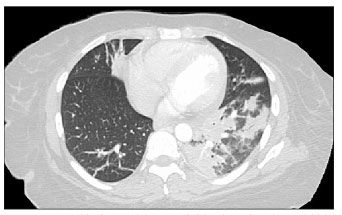

A chest radiograph and CT scan of the chest revealed infiltrates and adenopathies (Figures 1 and 2). A Gram stain of a sputum specimen revealed gram-positive filamentous rods (Figure 3). Bilateral pneumonia caused by N asteroides was diagnosed, and the patient was started on a regimen of ceftriaxone and trimethoprim/sulfamethoxazole (TMP/SMX), which resulted in significant improvement within a few days. Unfortunately, the patient signed out against medical advice and has been lost to follow-up.

Figure 2.CT scan of the chest revealed 2.8-cm right hilar adenopathy and 2.0-cm left hilar adenopathy with patchy areas of consolidation in the right upper, right middle, left lower, and lingular lobes.